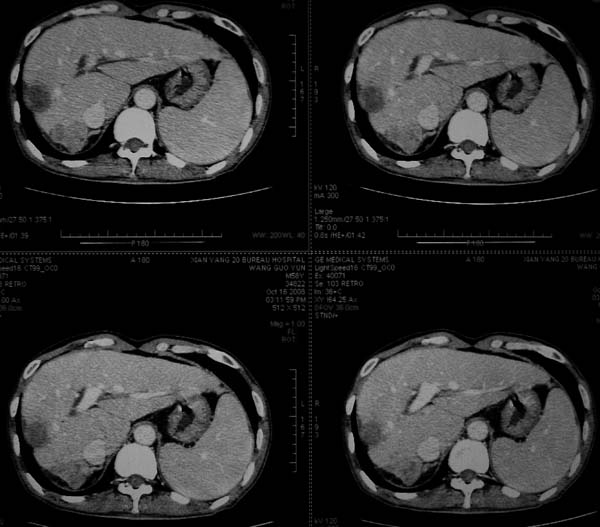

标题: CT16292:男,53岁,上腹部不适2月,B超发现肝内占位病变。 [打印本页]

标题: CT16292:男,53岁,上腹部不适2月,B超发现肝内占位病变。

象肝囊肿,有点黑,看不太清

符合肝ca增强,\"快进快出\";肝叶比例失常,右叶萎缩,肝裂增宽,脾大,肝硬化可能.

支持结节型肝癌。肝硬化脾大,病人是不是做过手术。

血管瘤,胆囊异位(图象很不清楚)。增强效果非常好,借鉴下!

肝脏体积变小,肝裂增宽,分布异常,肝尾叶增大,脾肿大,考虑肝硬化可能性大,右肝病灶呈现早期充盈,延迟强化考虑肝内胆管细胞癌可能,不除外血管瘤

肝硬、脾大,右肾在稍息,考虑结节型肝癌可能,不排除血管瘤。

支持 结节型肝癌;肝硬化、脾大。